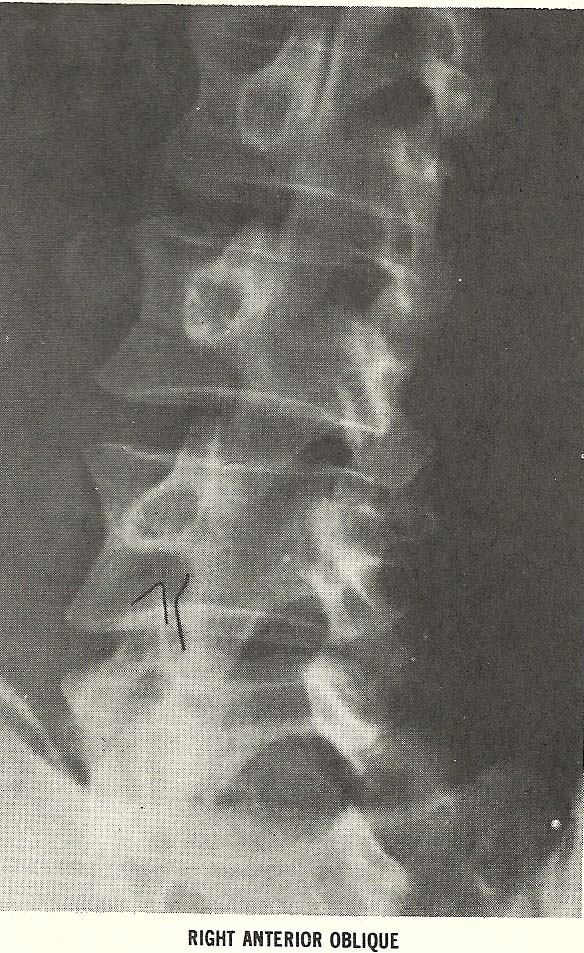

(Fig. 6.66), and similar alteration of the foramina at the same levels

are shown on the right anterior oblique film (Fig. 6.67), also meet the

criteria of subluxation under the classification of foraminal encroachment

(A-9).